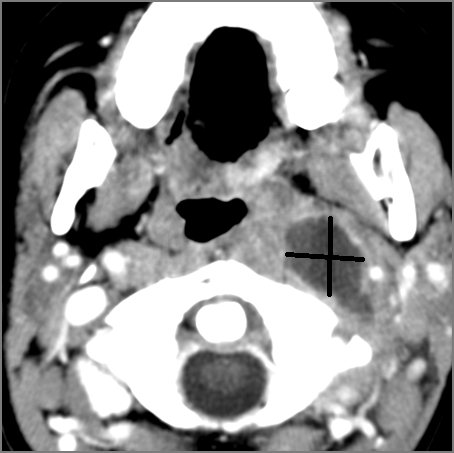

Cervical Lymph Nodes

If there is suppurative cervical adenopathy the purulent material outside the lymph node(s) capsule(s).